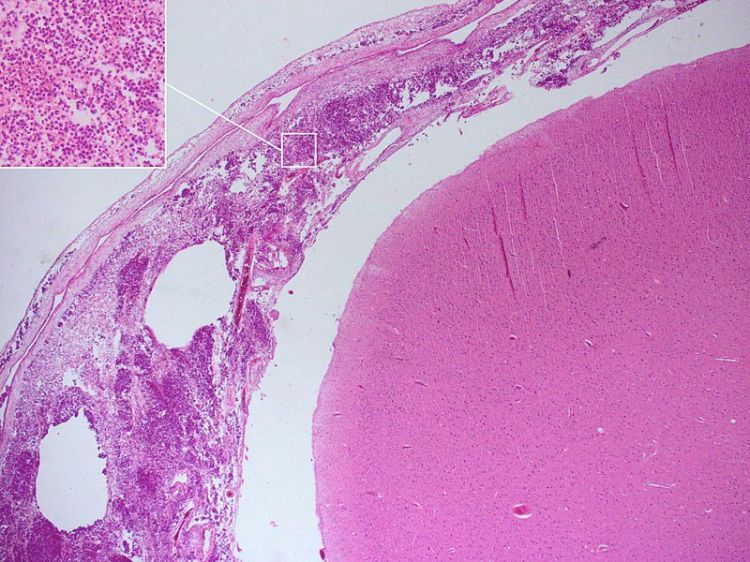

WikiWTF : Meningitis